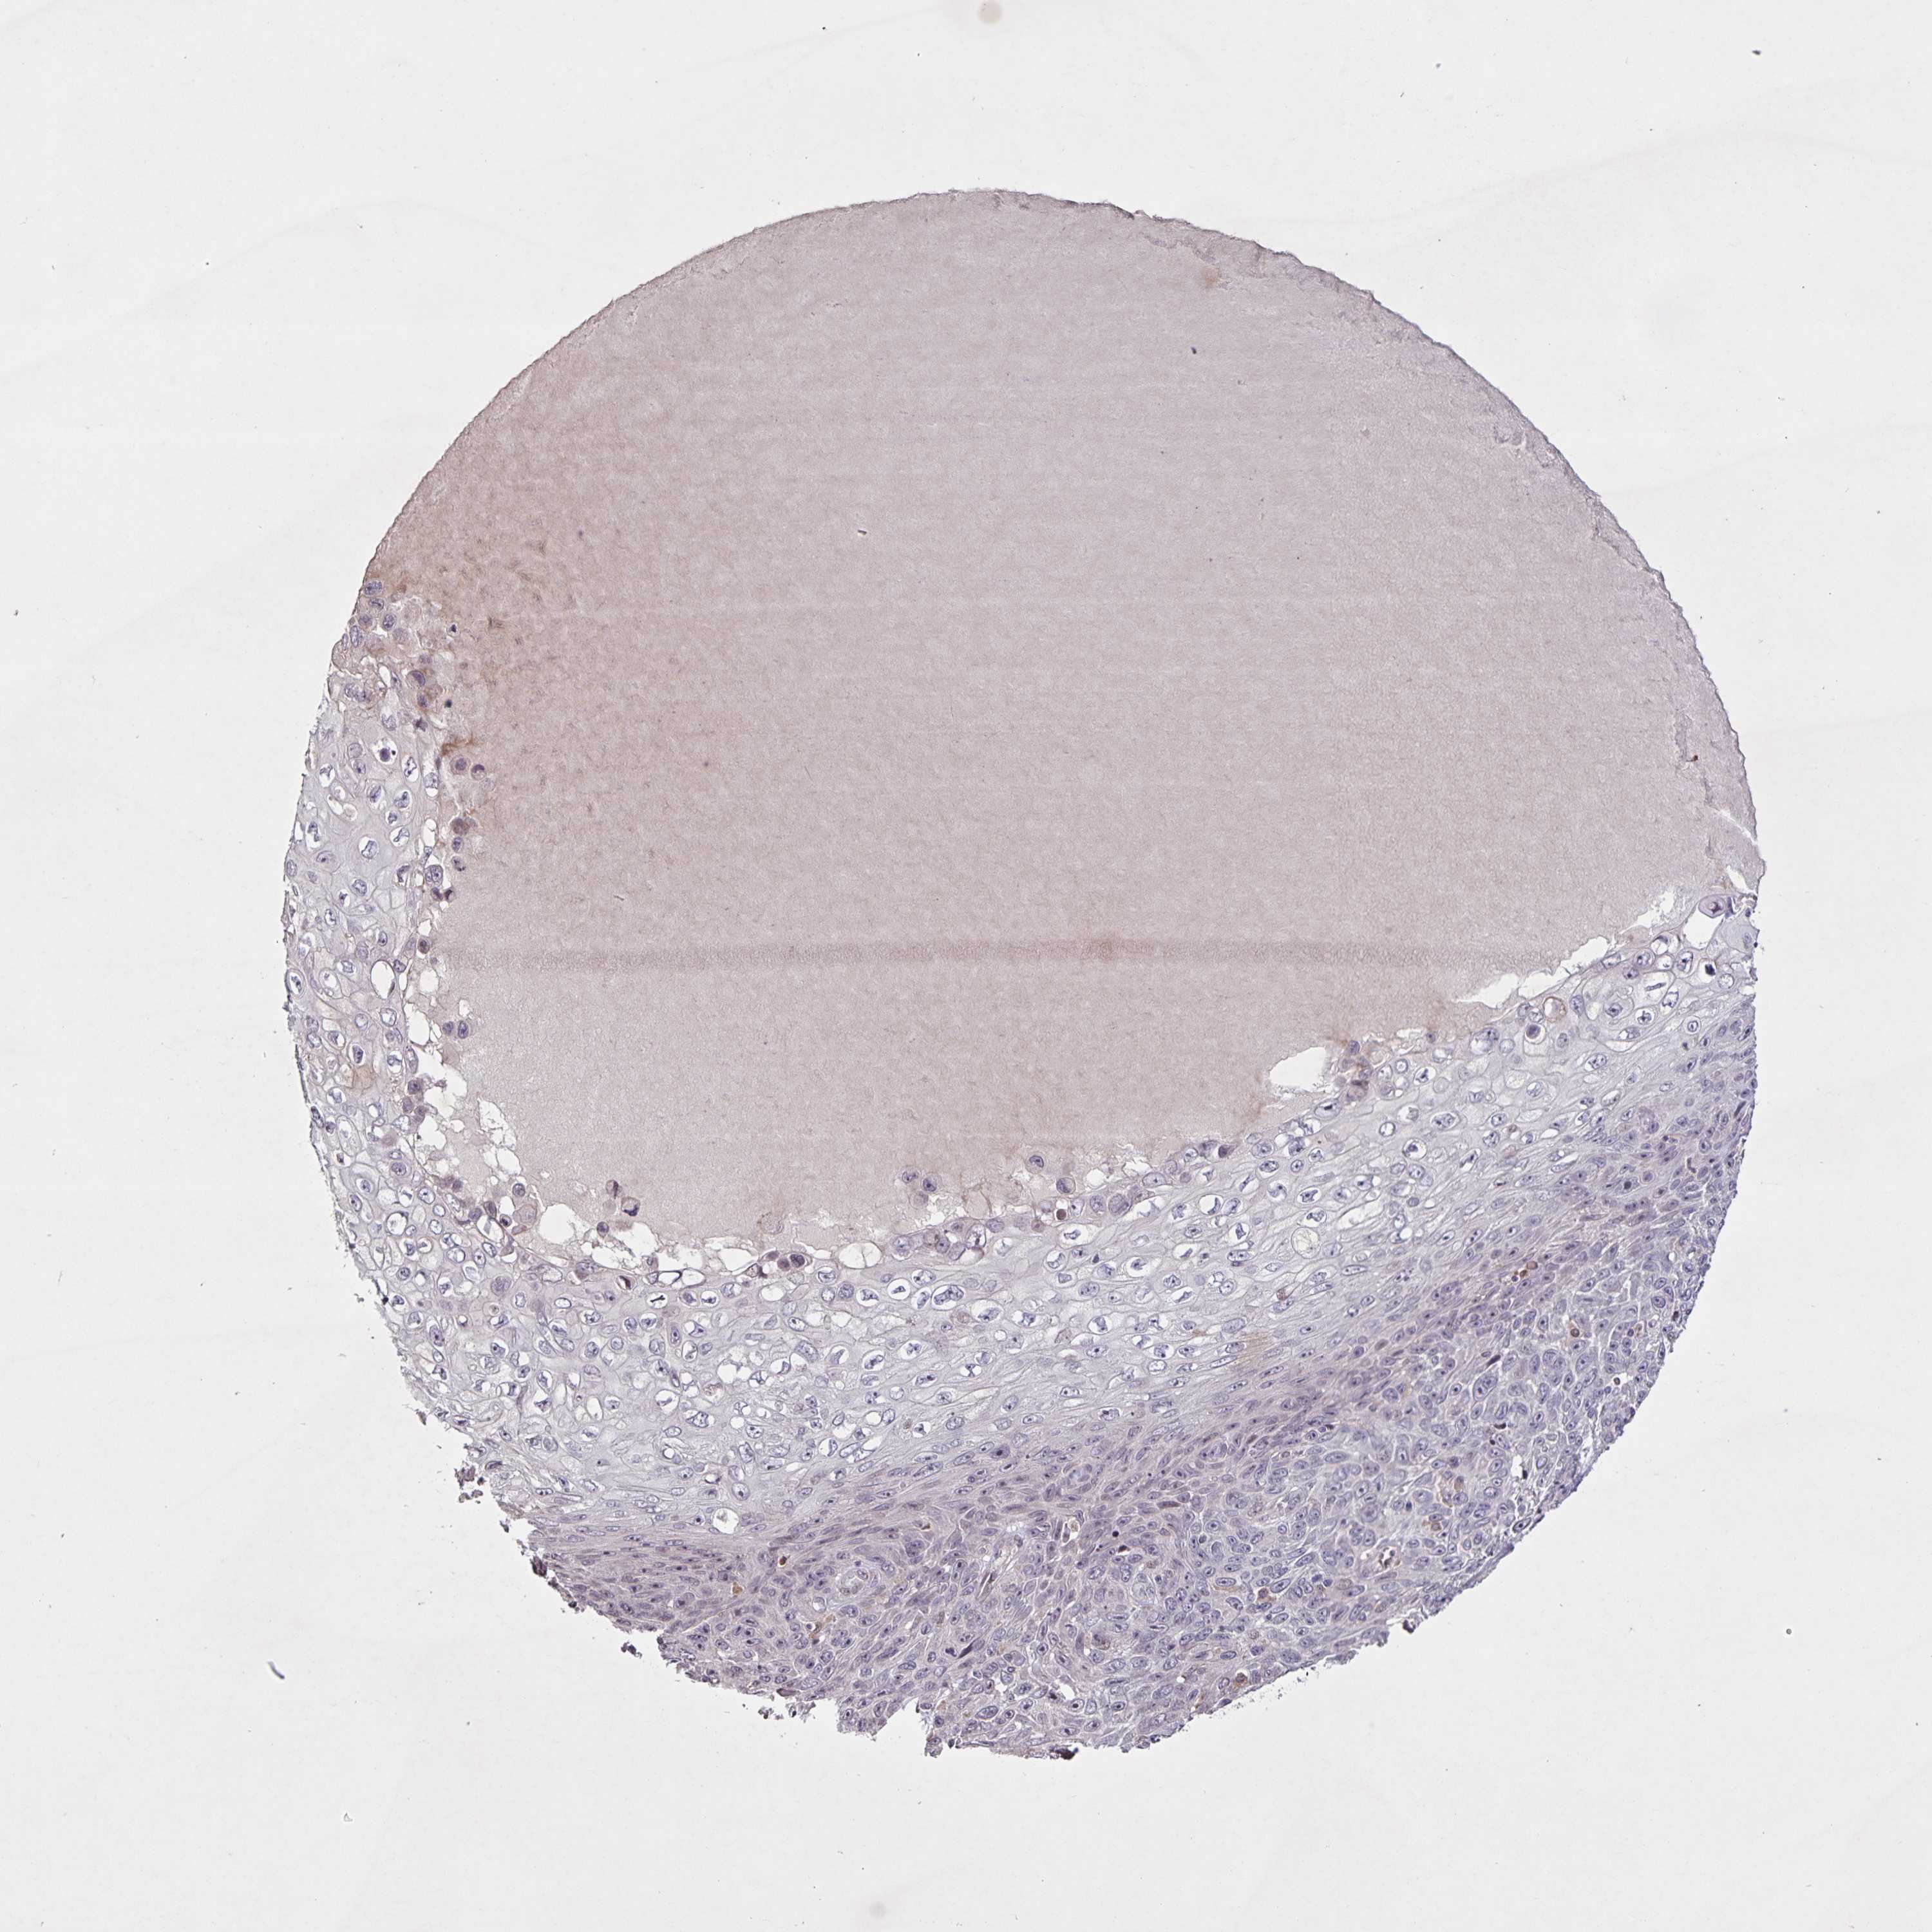

Basal cell and squamous cell cancer

SKIN CANCER - Protein expressioni

A mouse-over function shows sample information and annotation data. Click on an image to view it in a full screen mode. Samples can be filtered based on level of antibody staining by selecting one or several of the following categories: high, medium, low and not detected. The assay and annotation is described here.

Antibody stainingi

Antibody staining in the annotated cell types in the current human tissue is reported as not detected, low, medium, or high, based on conventional immunohistochemistry profiling in selected tissues. This score is based on the combination of the staining intensity and fraction of stained cells.

Each image is clickable and will lead to virtual microscopy that enables deeper exploration of all samples and also displays staining intensity scores, fraction scores and subcellular localization as well as patient and tissue information for each sample.

Antibody CAB023357

Staining

High

Medium

Low

Not detected

Intensity

Strong

Moderate

Weak

Negative

Quantity

>75%

75%-25%

<25%

None

Location

Nuclear

Cytoplasmic/membranous

Cytoplasmic/membranous,nuclear

Basal cell carcinoma

BCC, high aggressive

Squamous cell carcinoma, NOS